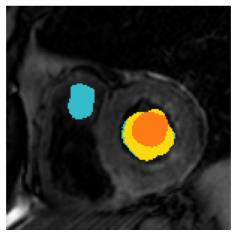

Although supervised deep-learning has achieved promising performance in medical image segmentation, many methods cannot generalize well on unseen data, limiting their real-world applicability. To address this problem, we propose a deep learning-based Bayesian framework, which jointly models image and label statistics, utilizing the domain-irrelevant contour of a medical image for segmentation. Specifically, we first decompose an image into components of contour and basis. Then, we model the expected label as a variable only related to the contour. Finally, we develop a variational Bayesian framework to infer the posterior distributions of these variables, including the contour, the basis, and the label. The framework is implemented with neural networks, thus is referred to as deep Bayesian segmentation. Results on the task of cross-sequence cardiac MRI segmentation show that our method set a new state of the art for model generalizability. Particularly, the BayeSeg model trained with LGE MRI generalized well on T2 images and outperformed other models with great margins, i.e., over 0.47 in terms of average Dice. Our code is available at https://zmiclab.github.io/projects.html.